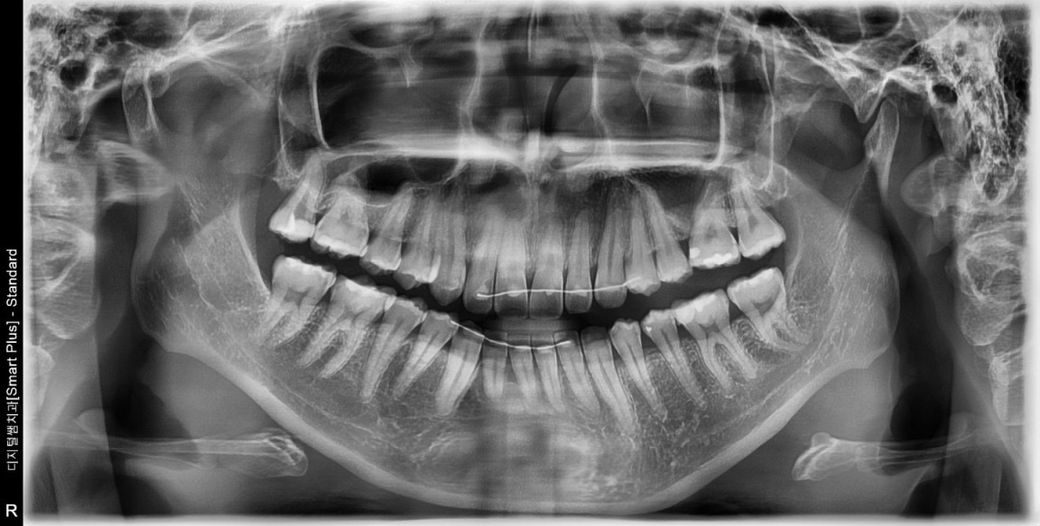

치아 어금니 충치 크라운 꼭 해야 할까요?

위에 맨끝 어금니가 겉으론 안보이고 안에서 충치가

생겼다고 하는데 신경치료를 꼭 해야 할 정도 일까요?

사진에서 보이는 왼쪽 위 젤 뒤 치아는 충치가 많이 깊어 보이는거 같습니다. 신경치료를 해야될 가능성이 높습니다.

충치가 깊어서 이미 엑스레이상 신경관이 노출된 것 같습니다 치수절제술(완전 신경치료)을 할지 아니면 치수절단술(부분 신경치료)을 할지의 고민이지 신경치료를 안할 순 없을 것 같습니다